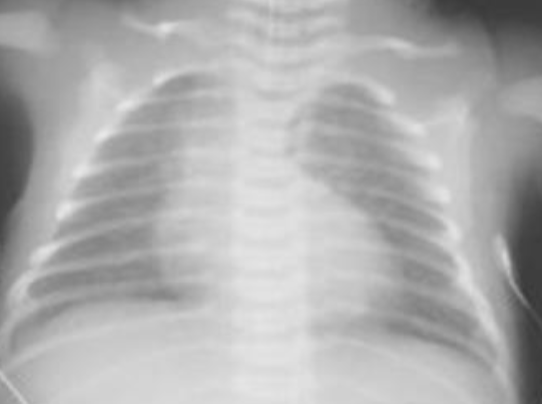

X-Ray with Consolidation:

- What is the diagnosis? Pneumonia

- What is the causative organism? Streptococcus Pneumonia